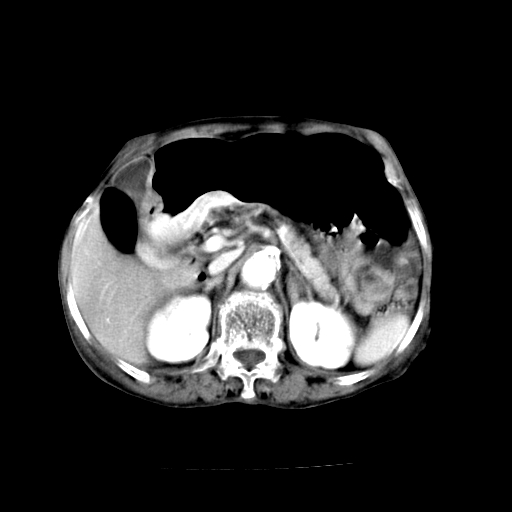

女,68岁,腹胀、恶心两周,先做ct平扫,当时家属不同意强化,6天后家属要求增强扫描。

1、胃窦癌; 2、局灶性脂肪肝。

1、胃窦癌?建议行胃镜!; 2、局灶性脂肪肝。

考虑:胃窦ca,腹水,脂肪肝

1)胃窦壁厚,考虑胃窦癌?建议行胃镜检查。 2)局灶性脂肪肝。